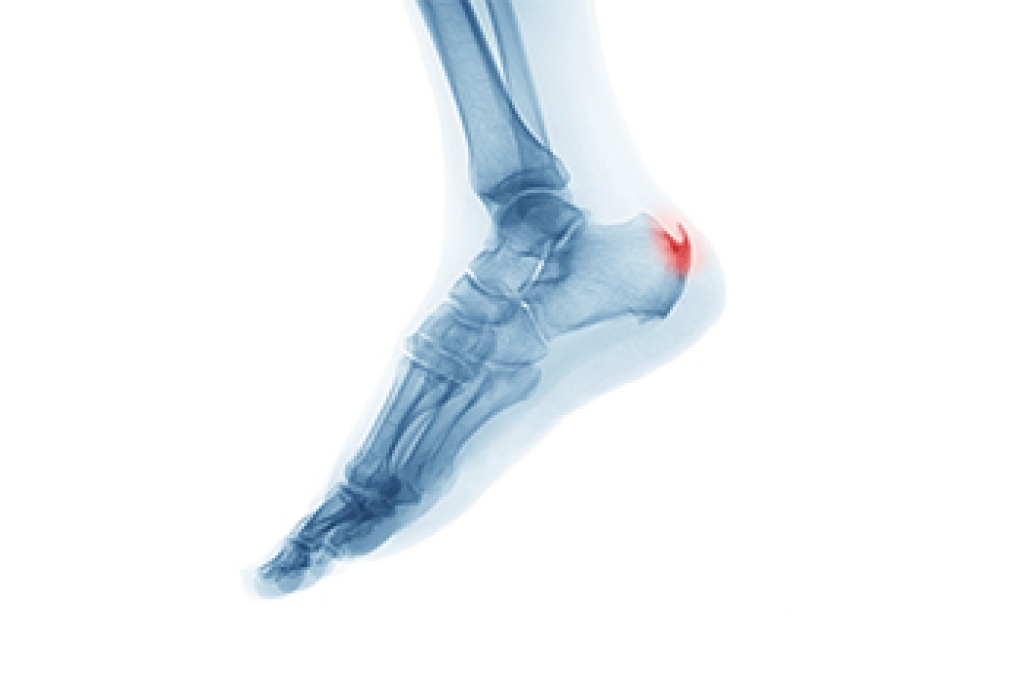

A heel spur develops between the heel and arch of the foot. It is a calcium deposit that is often accompanied by severe heel pain. Heel spurs can appear to be pointy or hooked and can be up to a half-inch long. Heel pain often requires a visit to the podiatrist, who can effectively diagnose the cause. This can be done by having an X-ray, which can help rule out other foot conditions. Many people develop heel spurs from wearing shoes that do not fit correctly. This can cause strain on the muscles and ligaments and can gradually wear out the soft tissues. Additional reasons why heel spurs can develop may include being overweight and frequently participating in running and jumping activities. Resting the affected foot may provide temporary relief, and it may help to wear shoes that have a cushioned heel. If you have heel pain, it is suggested that you consult with a podiatrist who can offer you options for permanent relief.

Heel spurs are formed by calcium deposits on the back of the foot where the heel is. This can also be caused by small fragments of bone breaking off one section of the foot, attaching onto the back of the foot. Heel spurs can also be bone growth on the back of the foot and may grow in the direction of the arch of the foot.